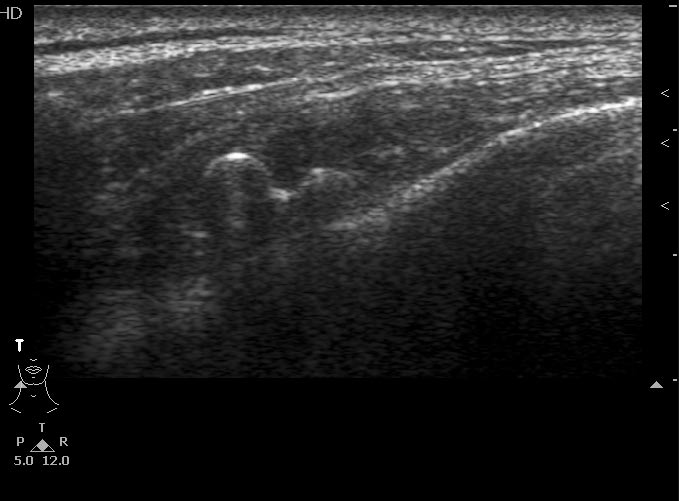

Выкладываю данные КТ

На снимке утолщение веретенообразное мышечного слоя с наличием кальцификатов(два) Кальцификаты в мышце чаще встречаются при паразитарных инфекциях(трихиниллез,токсоплазмоз,цистецеркоз),но их больше по количеству и в разных местах.Оссифицирующий миозит-имеет свою картину и распространение.Насчет Хортона-навряд ли,это же поражение сосуда.Насчет тофусов-они содержат ураты,чаще локализуются подкожно(не в мышце),при подагре осификации вдоль сухожилий.А может был удар,гематома с частичной кальцификацией?

Плотность не соответствует дроби, она более денсная и даёт артефакты.